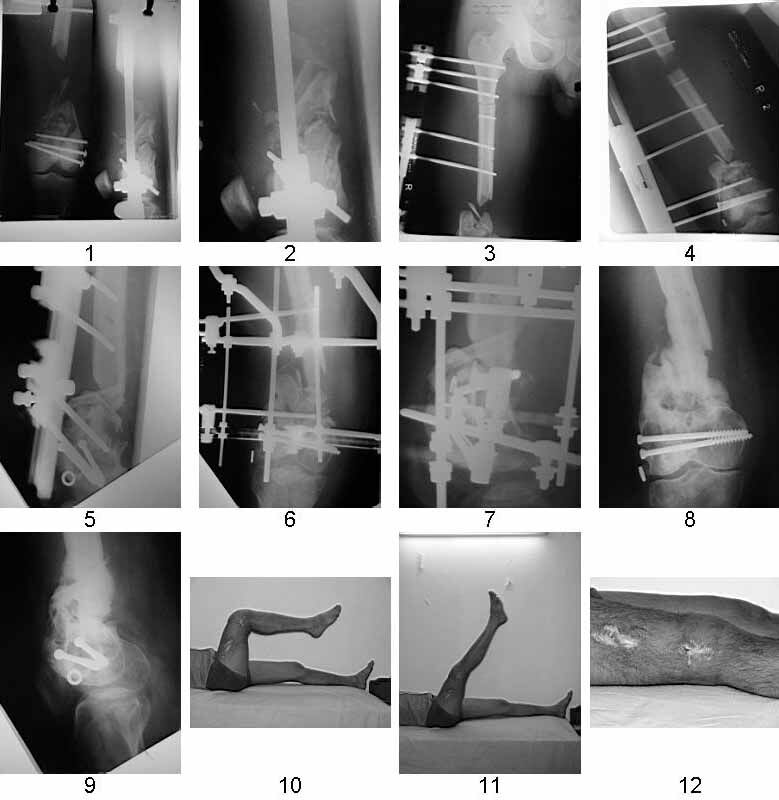

Similar case.

They do well with bone transport.

I do an acute or accelerated shortening to reduce the gap as much as proximal, and distract proximally to restore length.

In this particular case, notice the change of fixator - orthofix type of unilateral fixator worked well initially but did not allow me to compress beyond a point, which is when I changed to an ilizarov for further compression at the gap/nonunion site.

Mangal Parihar

Orthopedic surgeon, mumbai